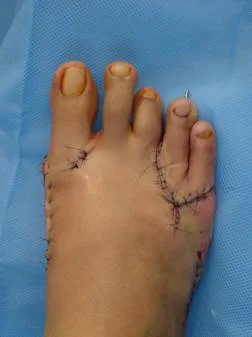

Hallux Valgus

Hallux valgus. Caso clínico:

Paciente femenino de 32 años de edad, quien consulto por dolor en pie derecho, secundario a hallux valgus por metatarso primo varo. Fue intervenida quirúrgicamente con excelentes resultados. Ver más.